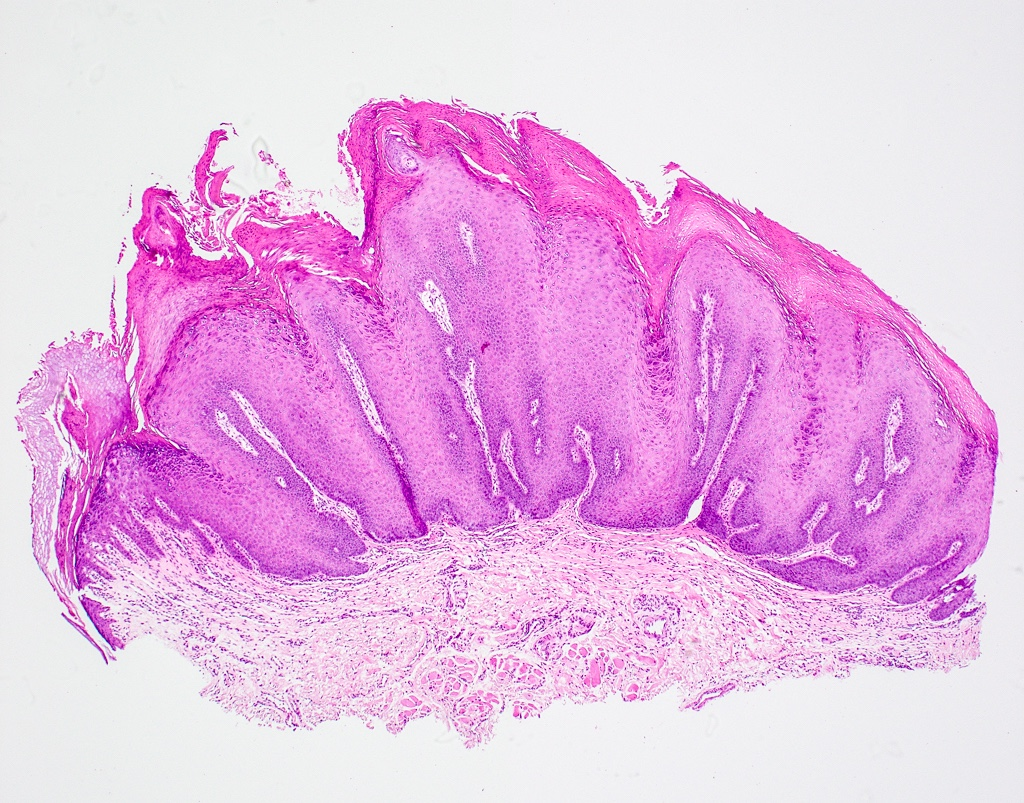

| papilloma (6, 11) |

30~50y | 軟顎、口腔常見 | 單發、低傳染 | |||

pedunculated, sessile(少)  |

| stratified squamous epi. 包結締組織 hyperparakeratosis (有核、顆粒層缺失)  |